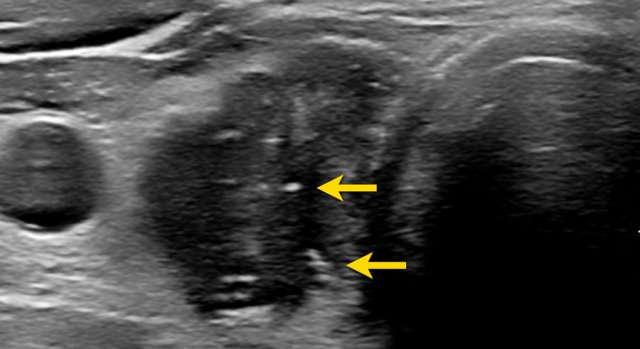

Very hypoechoic , i.e. 3 points in TI-RADS. Very hypoechoic , i.e. 3 points in TI-RADS.

A very hypoechoic lesion is more hypoechoic than normal muscle.

Notice that the tumor is more hypoechoic in comparison to the strap muscles (arrows).